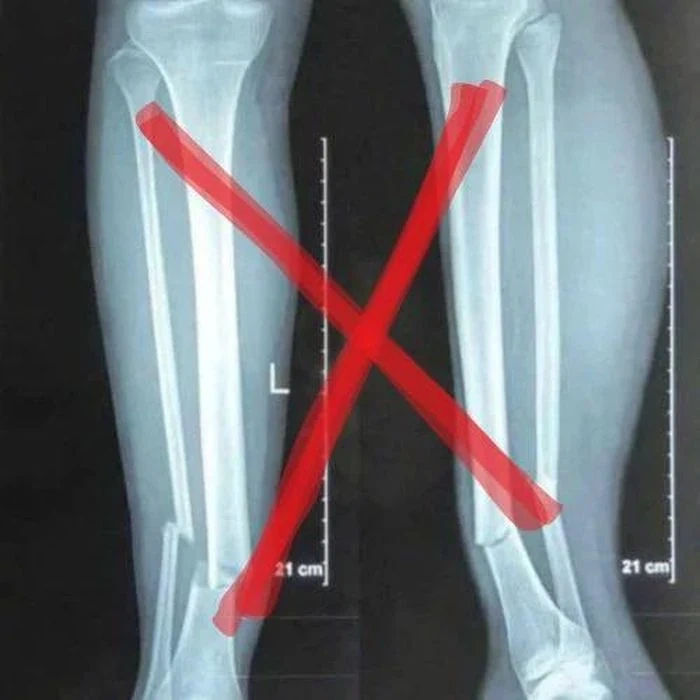

Theo kết quả từ bệnh viện Thái Lan, chấn thương của Nguyễn Xuân Son ở phút 32 trong nỗ lực đi bóng tốc độ và cố tạt bóng vào đã bị gãy xương mác và xương chày. Tại nạn này xảy ra khi sau động tác tạt bóng và mất trụ, chân phải của Xuân Son đã bị gập xuống mặt cỏ.

Đây mới chính là kết quả chụp phim của Xuân Son chụp lại máy tính bệnh viện

Trường hợp của Nguyễn Xuân Son theo các bác sĩ thì nếu không có các tổn thương khác như dây chằng khớp gối mà chỉ là gãy xương chày và xương mác thôi thì sau khi giải phẫu cố định xương đúng vị trí sẽ kết hợp giữa hồi phục và tập luyện thì mất từ 6 tháng đến 1 năm có thể thi đấu bình thường trở lại.